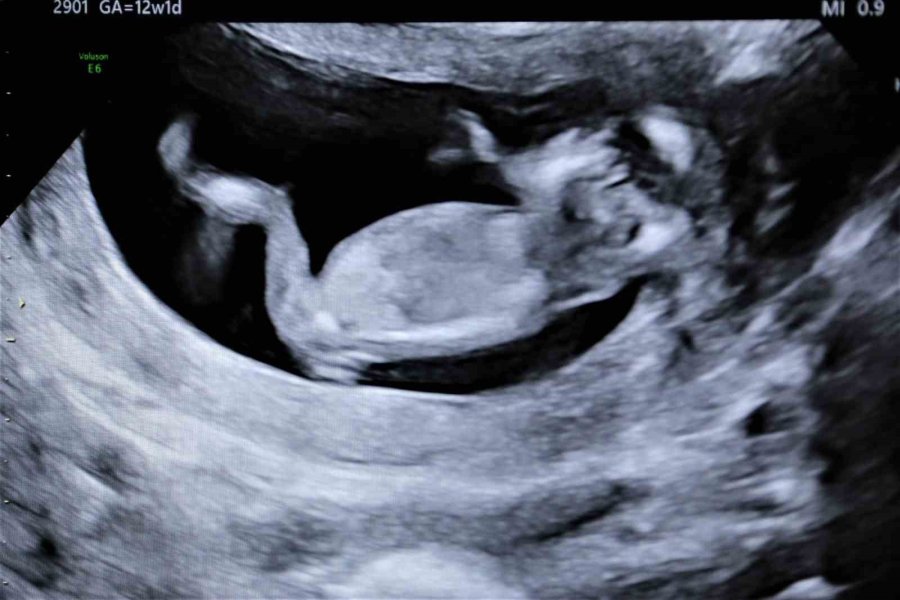

’gebelikte Her Balığın Eti Yenmez’ Uyarısı

Anne adayları için tüketilmesi gereken sağlıklı gıdalar kadar, tercih edilmemesi gereken gıdalar da önemli. Uzmanlara göre, gebelikte bazı balıkların yenilmesi bebeklerde sorunlara neden olabiliyor. Örneğin cıva miktarı yüksek olan, köpek balığı, kılıç balığı gibi ürünlerdeki cıva, plasentadan bebeğe geçerek bilişsel becerileri, motor becerileri, dil becerileri ve görme yeteneği üzerinde olumsuz etkiler yapabilmektedir.

"Gebe kalmadan 3 ay önce folik asite başlar ve gebeliğin 3'üncü ayına kadar devam ederse bebekte beyin omurilik sıvı defektleri yüzde 50 azalabilir. Bunu mutlaka yapmak lazım. Protein kaynaklarını çok iyi almaları gerekir. Aynı zamanda omega 3 bebeğin beyin gelişimi açısından da çok önemlidir. Kesinlikle haftada 2-3 porsiyon balık tüketilmelidir. Normal sezon balıkları tüketilebilir" şeklinde konuştu.

Hamilelikle folik asitin önemi hakkında bilgi veren Kumru, "Folik asit eksik olması durumunda sorunlu gebelik olabiliyor. Gebe kalmayı düşünendenler gebelikten en az 4 ay önce 0,4 miligram kullanmaya başlamalıdır. Gebeliğin 12'nci haftasına kadar devam edecek. Uzak durulması gerekenler ise deniz ürünlerinin bir kısmından uzak durulması gerekir. Dipte yaşayan deniz ürünleri bünyelerinde cıva barındırabilirler. Cıva bizim gebelikte istemediğimiz bir şeydir. Bebekte cıva zehirlenmesi olabiliyor" sözlerine yer verdi.